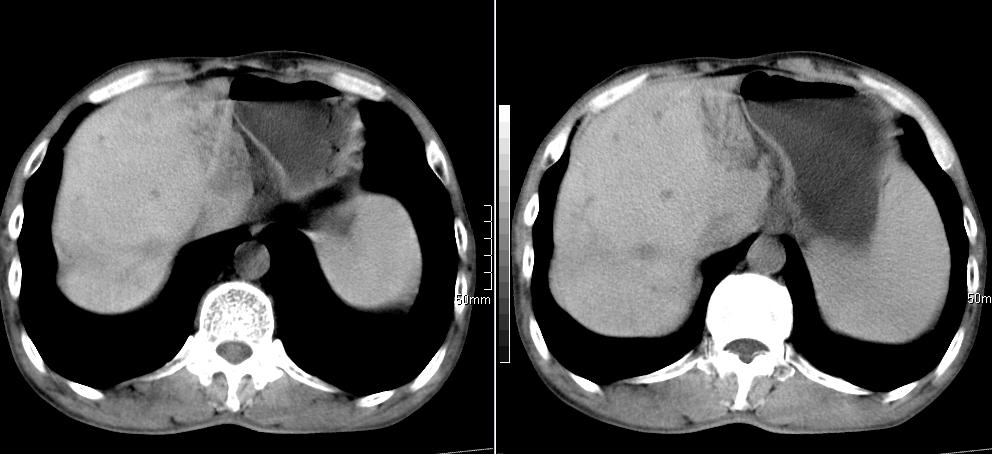

标题: CT26769:男,58岁,腹胀、腹部不适一年余 [打印本页]

标题: CT26769:男,58岁,腹胀、腹部不适一年余

肠系膜脂膜炎,胆囊炎,脾大。建议结合临床。鉴别:慢性胰腺炎并假囊肿形成。

1 慢性胰腺炎并假囊肿形成。2 慢性胆囊炎并累及肝边缘!

1)考虑慢性胰腺炎并假性囊肿形成。2) 慢性胆囊炎。3)肝内胆管扩张。

1肝内胆管扩张,性质待定,2慢性胰腺炎胰管扩张,胰腺颈部假囊肿,3肝左叶低密度为小囊肿,4胆囊炎。

1)考虑慢性胰腺炎并假性囊肿形成。2)肝内胆管稍扩张。